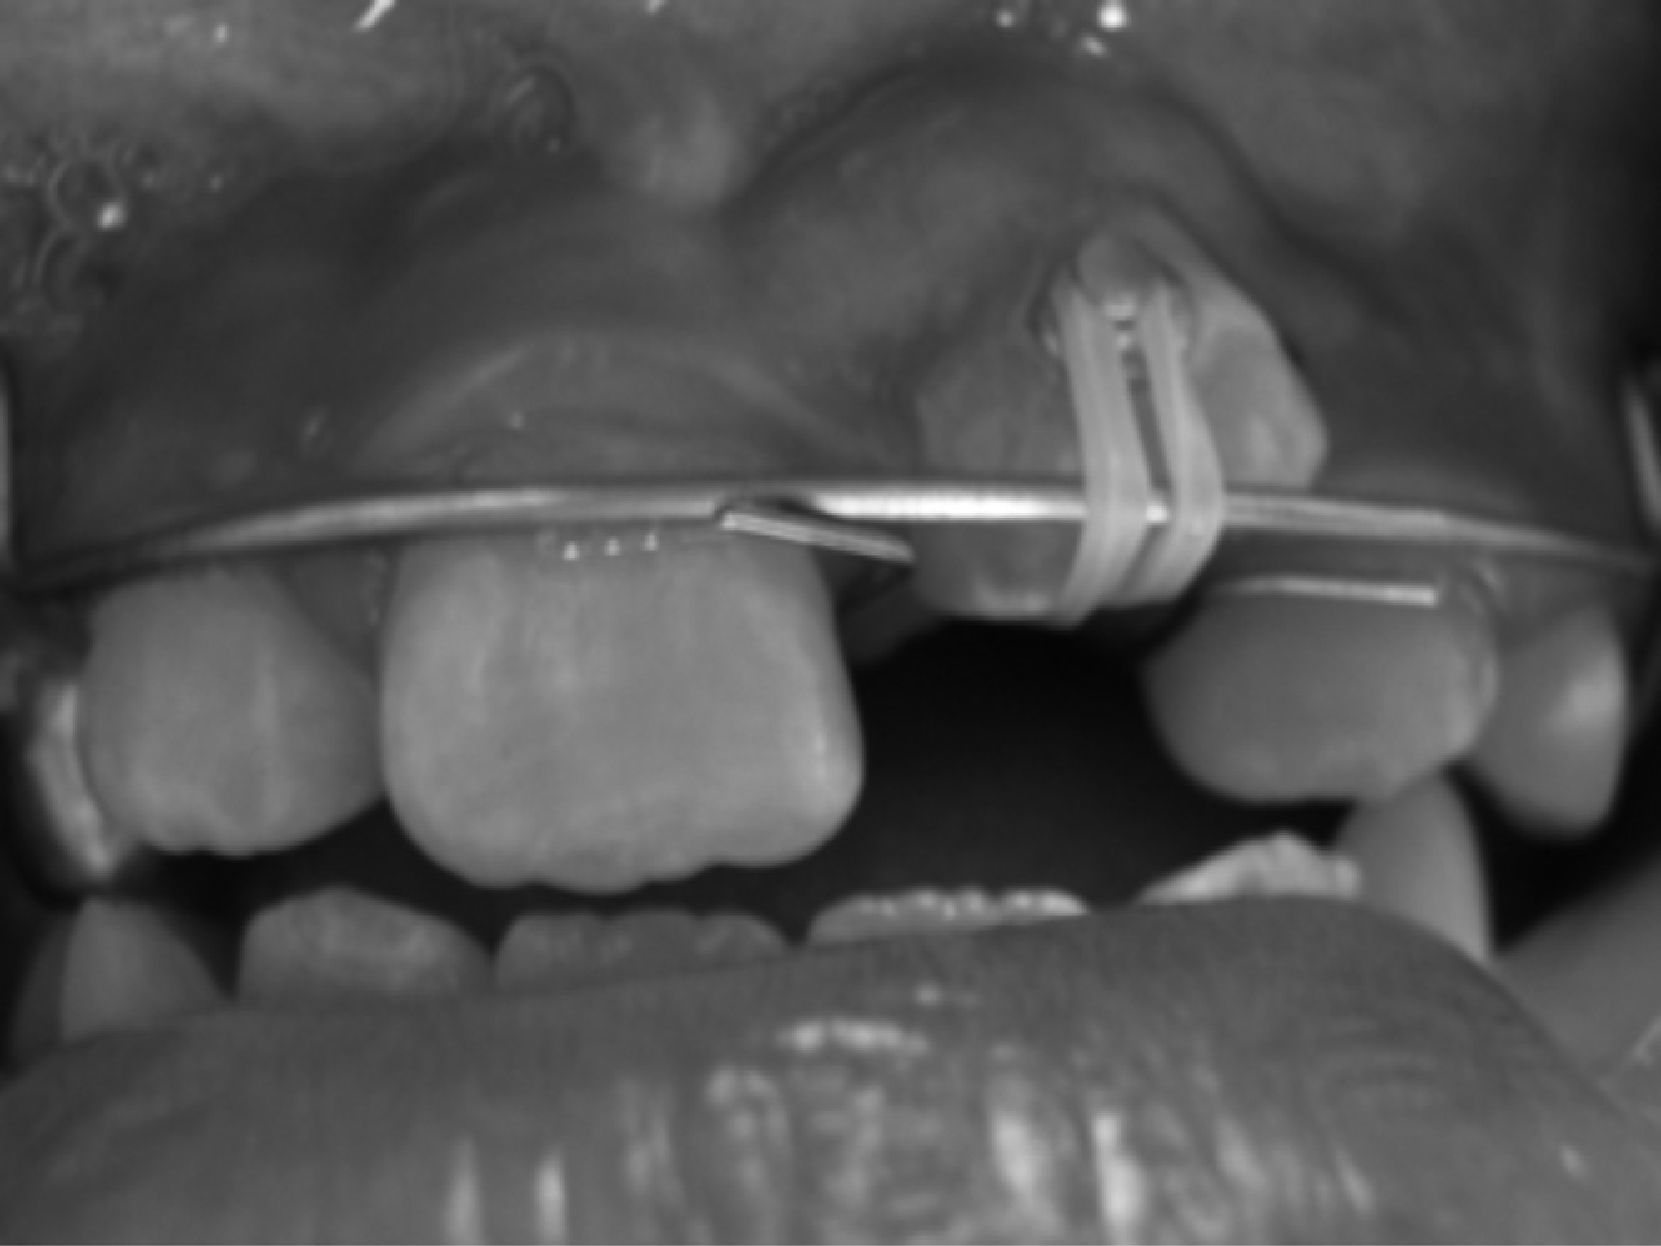

Previa asepsia y antisepsia de la región, se infiltró anestésico y se descubrió la corona del diente impactado, facilitando con ello la eliminación quirúrgica del mismo y permitiendo el acceso directo al incisivo impactado y la colocación del botón para su posterior tracción. El diseño de la incisión se hizo de tal forma que conservara el frenillo labial y la mayor cantidad de encía insertada para el levantamiento de un colgajo de espesor total3,11,12,14,15 (fig. 2).

Se realizó la exposición del borde incisal del incisivo impactado, observándose buena cantidad de encía insertada y boton con malla en adecuada posición para iniciar traccion del diente impactado (fig. 3).